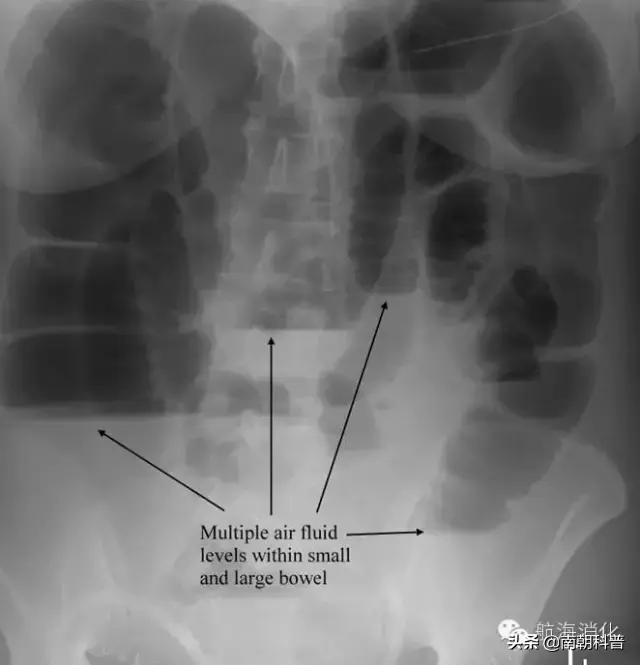

浠讳綍涓嶆槑鍘熷洜鐨勮吂鐥涳紝搴斿父瑙勮吂閮ㄥ钩鐗囨鏌ャ€傝吂鐥涘悗4-6灏忔椂鍑虹幇姘旀恫骞冲拰鏄庢樉鑲犵绉皵鎵╁紶鏃讹紝鍗冲彲璇婃柇鑲犳闃伙紝鍚屾椂锛岃繕鍙尯鍒槸灏忚偁姊楅樆杩樻槸澶ц偁姊楅樆銆佹満姊版闃昏繕鏄夯鐥规闃伙紝鍔ㄦ€佽瀵熷彲鍙嶆槧鑲犳闃荤殑鐥呮儏鍙樺寲锛屽洜姝わ紝鑲犳闃诲彂鐢熷悗鏈€濂芥瘡1-3澶╂媿涓€寮犺吂閮ㄥ钩鐗囷紝鐩村埌姘旀恫骞冲拰鑲犵Н姘旀秷澶便€?/p>